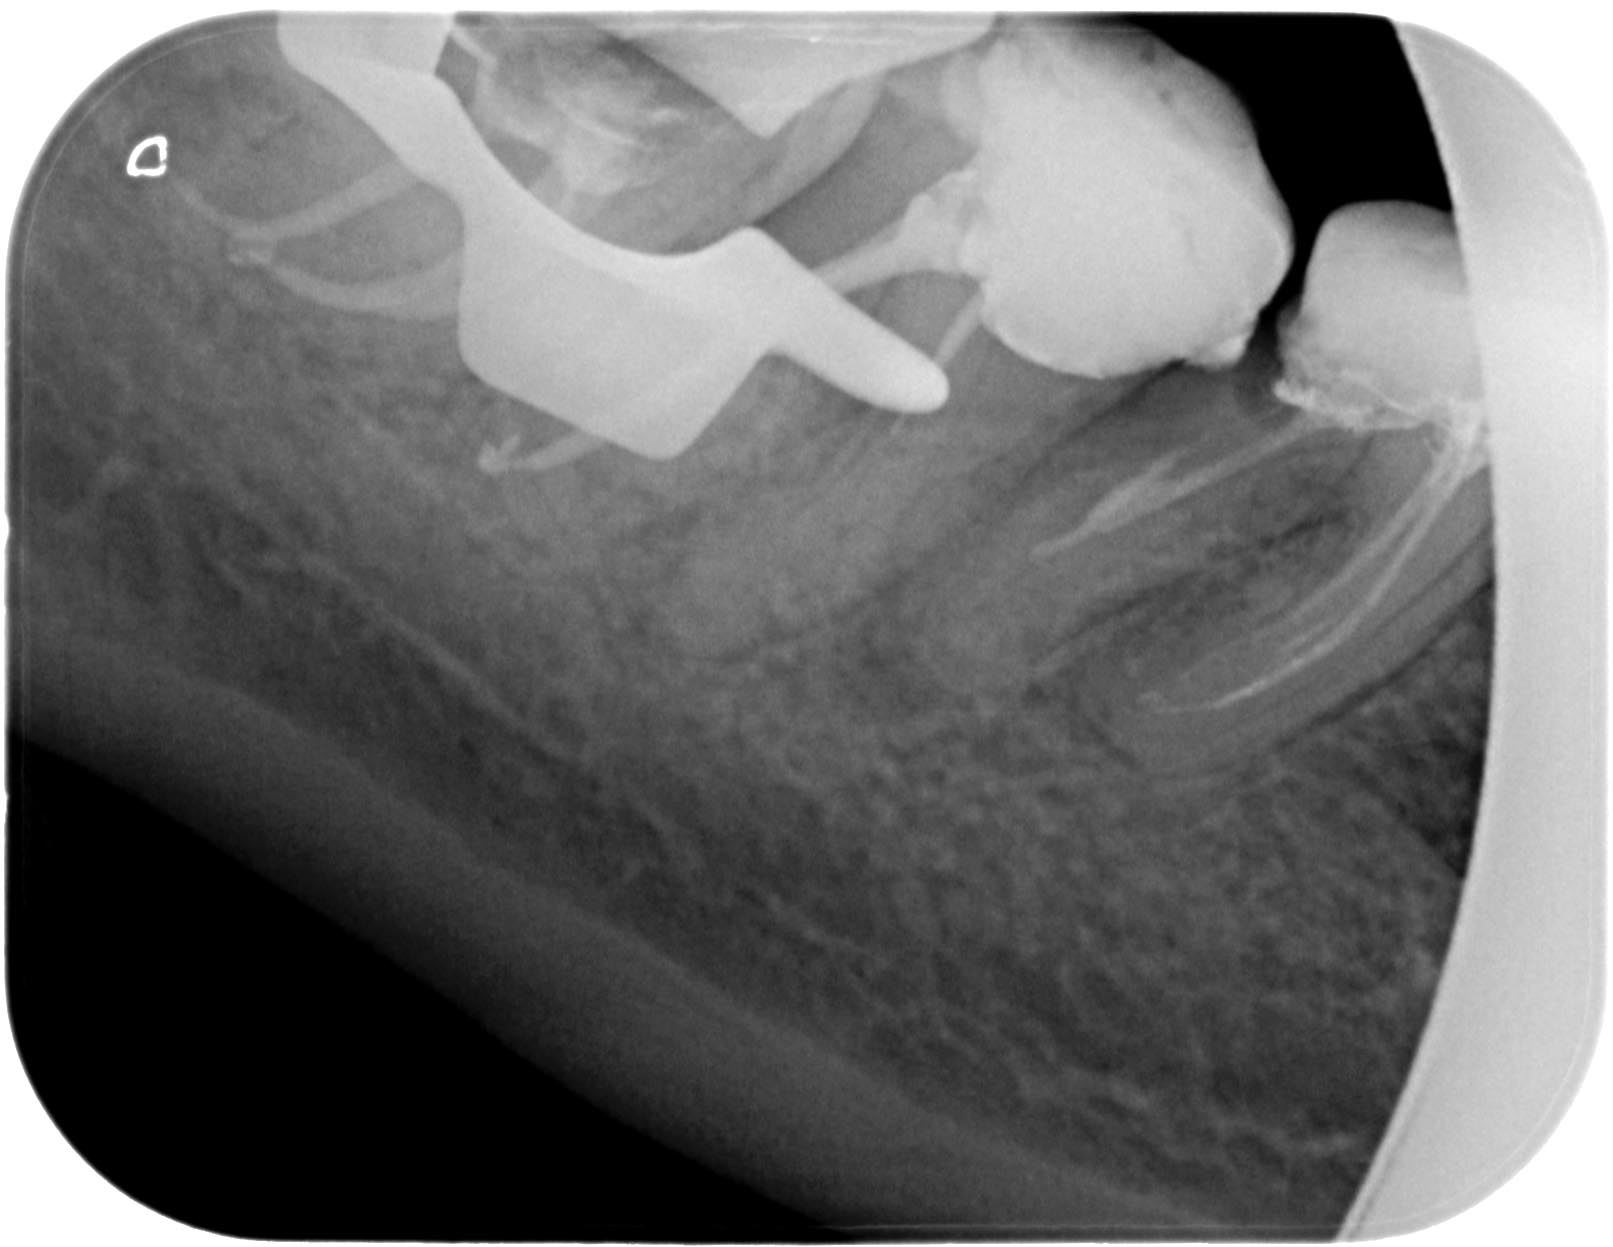

48-1-5 Veröffentlicht 8. Mai 2011 am 1613 × 1247 in Wurzelkanalbehandlung 48 mit RACE 02, MTwo und VDW Reciproc